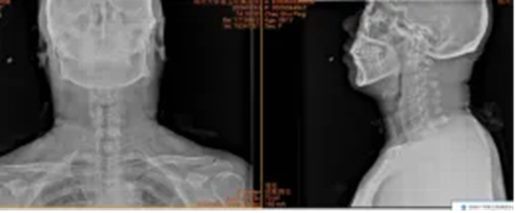

3.湖北省十堰市许先生53岁

术前:依托高分辨率CT、MRI及神经电生理监测,进行三维可视化手术规划

术中:在超声骨刀辅助下开展颈前路、颈后路或后路+前路等术式,并在神经电生理监护下确保减压彻底、置钉安全。